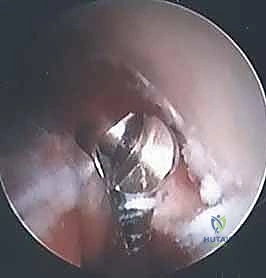

* يُستخدم الثقب الأول لإدخال كاميرا المنظار عالية الدقة (بتقنية 4K) التي تنقل صورة مكبرة وواضحة جداً للمفصل من الداخل على شاشة عملاقة.

* يُستخدم الثقب الثاني لإدخال الأدوات الجراحية المجهرية الدقيقة.

3. الفحص والاستكشاف المجهري

أولى خطوات النجاح هي الرؤية الواضحة. يسمح المنظار للدكتور هطيف بفحص مفصل المرفق من الداخل بالكامل، للتأكد من عدم وجود مشاكل أخرى مرافقة (مثل قطع غضروفية سائبة، أو التهابات في الغشاء الزليلي).

4. تحرير الوتر المتضرر (ECRB Release)

بمجرد تحديد موقع الجزء المتضرر والتالف من وتر العضلة الباسطة الرسغية القصيرة (ECRB)، يقوم الدكتور هطيف بمهارة عالية بـ "تحرير" أو قطع هذا الجزء المريض فقط، مع الحفاظ التام على الأوتار السليمة المحيطة به (مثل EDC). إزالة هذا النسيج التالف الوعائي الليفي هو ما يقضي على مصدر الألم.